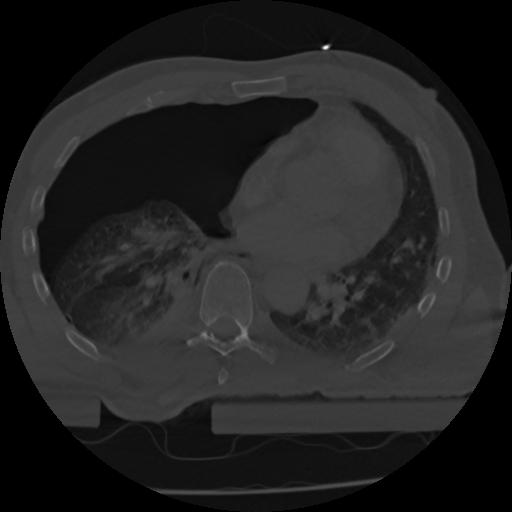

22 ANGIO,CE,Vol,0.5,ANGIO,,